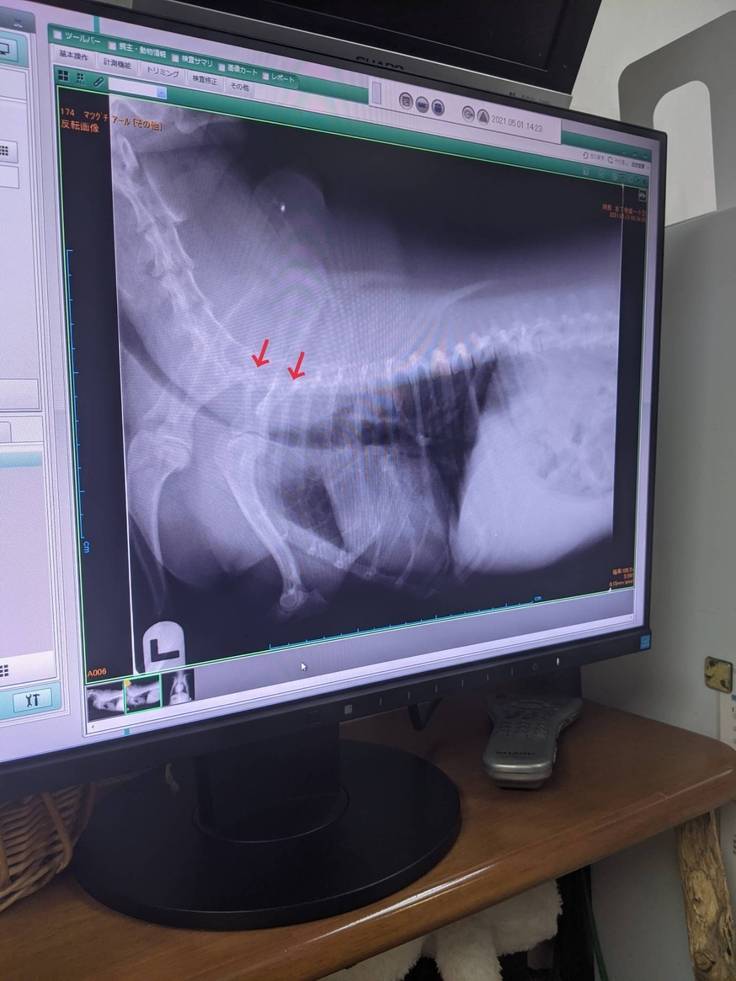

診断書

去年10月末、2月中旬、4月は2回、動物病院で診察を行って頂き検査で重度レベル4気管の75%以上虚脱状態とわかりました。

↓の画像